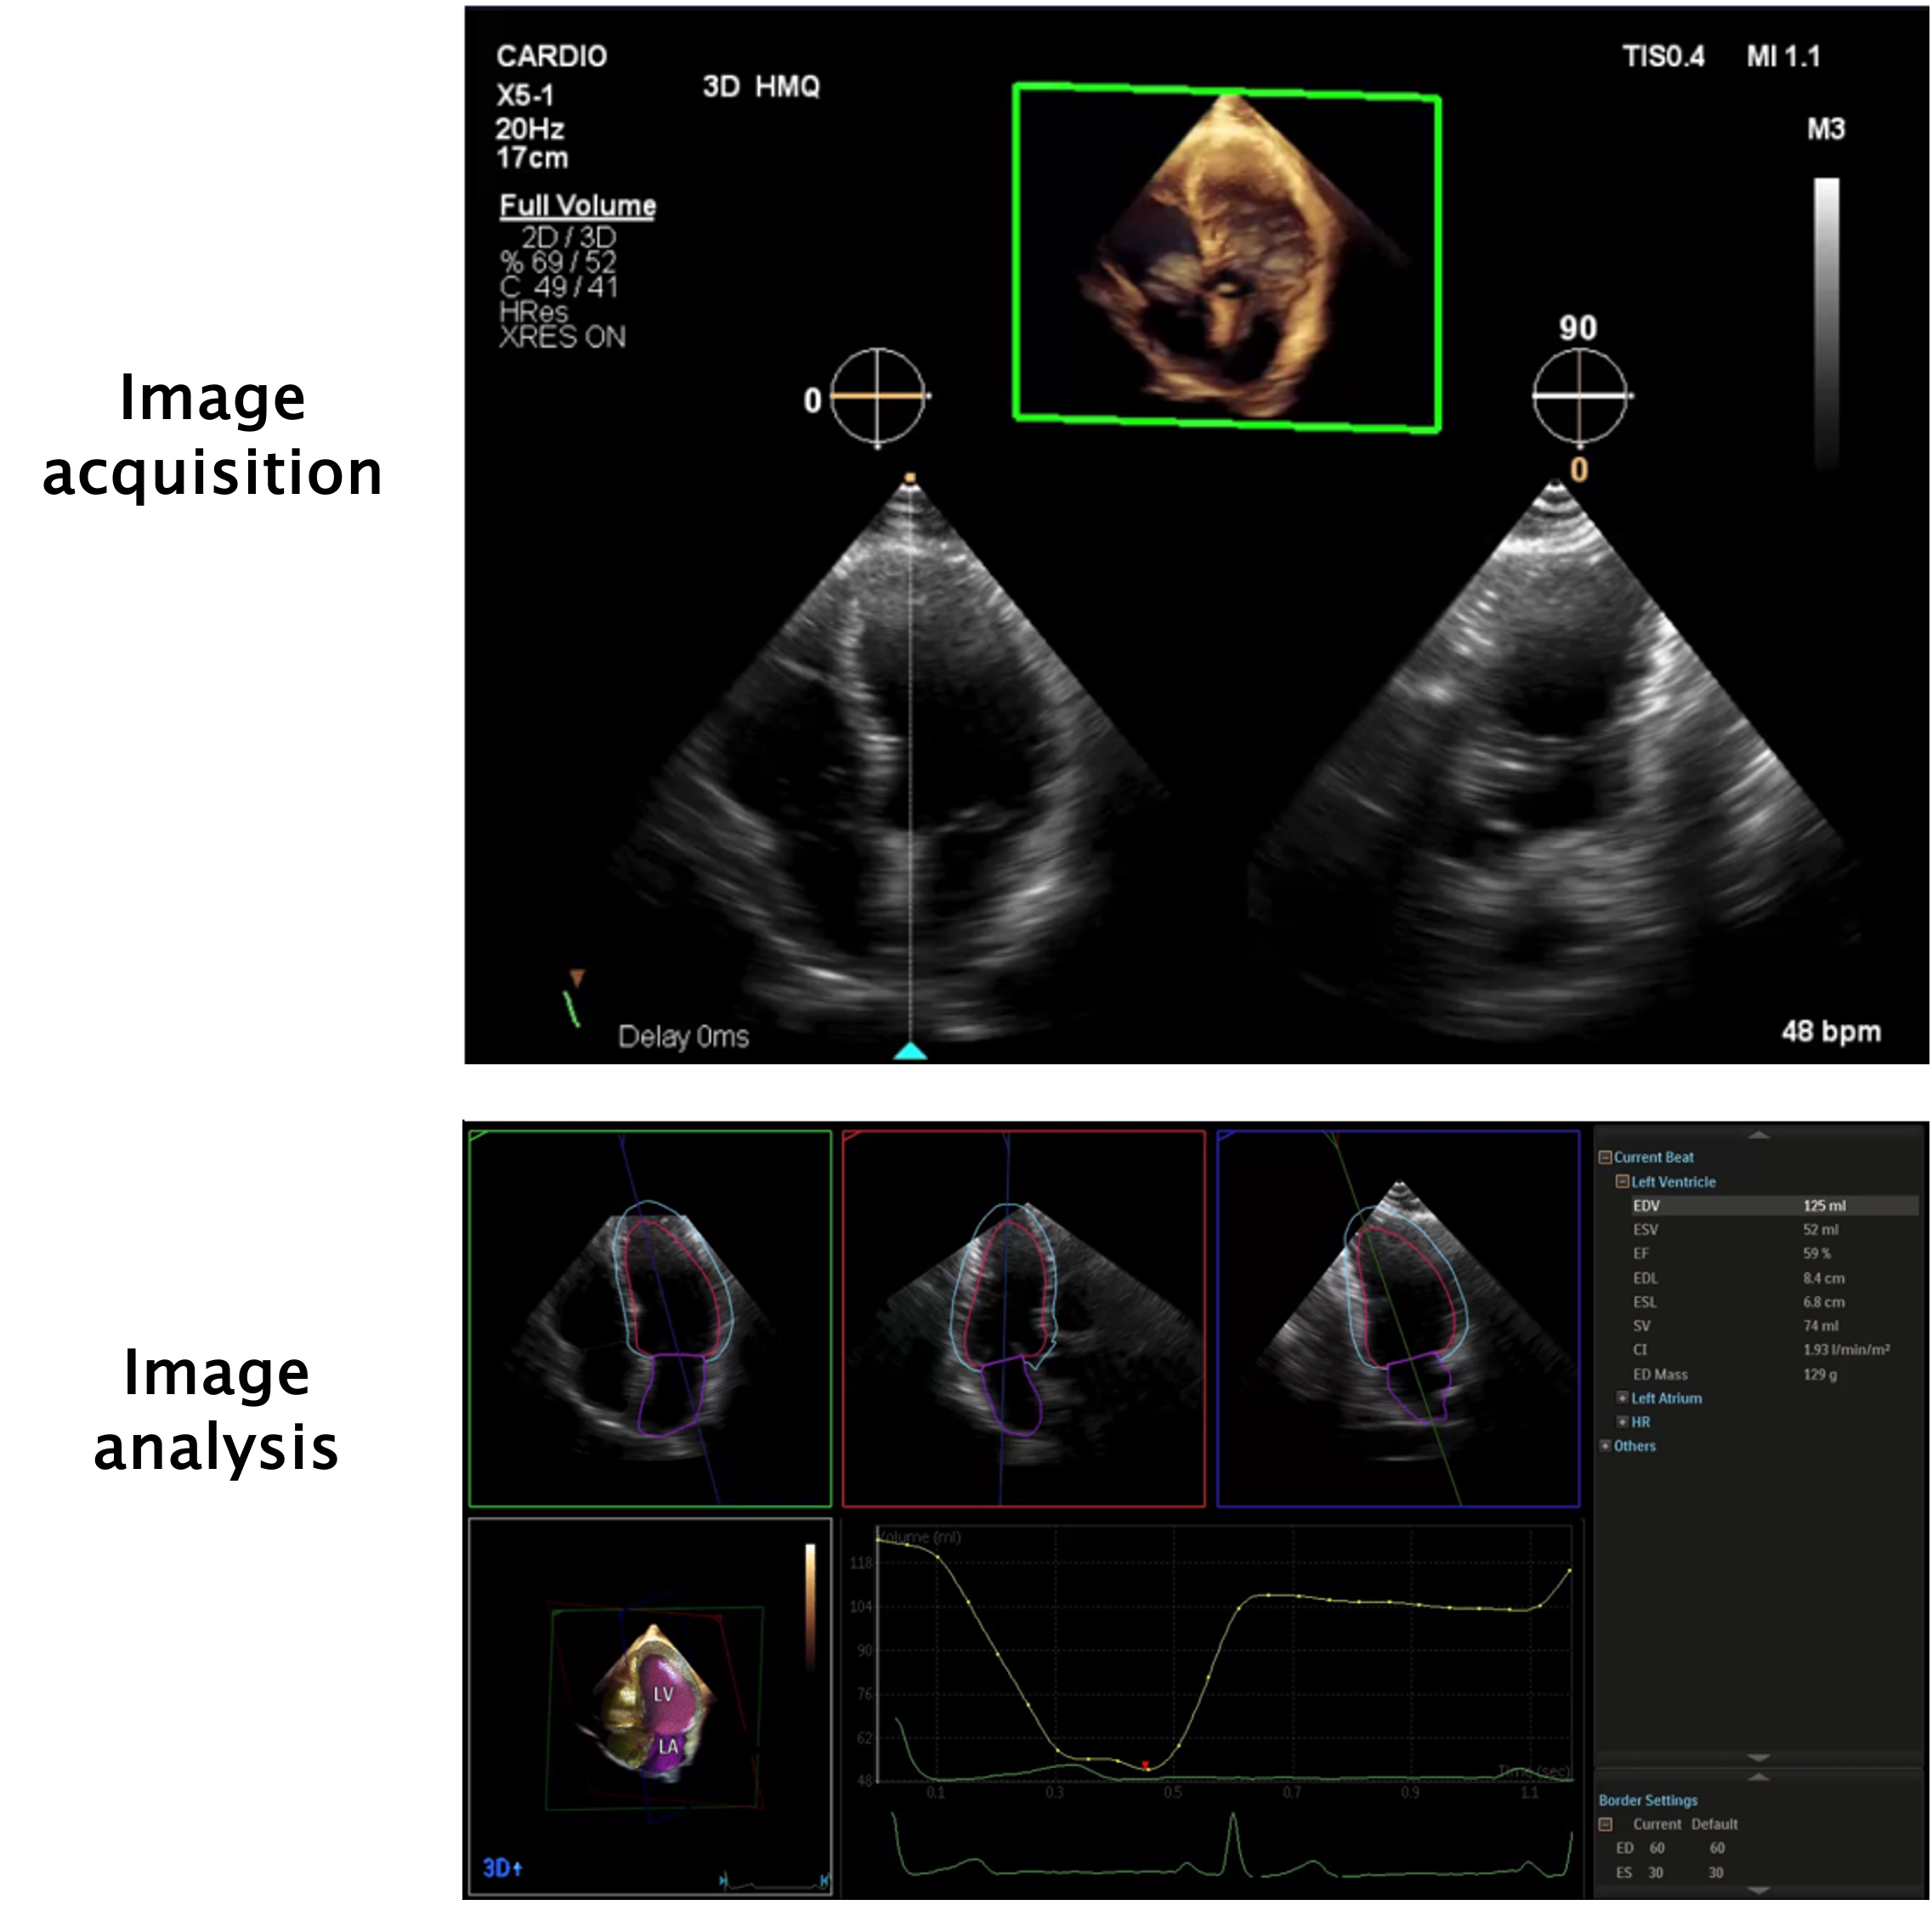

Artificial intelligence is already in place in several echocardiography laboratories. For every TTE performed there are AI algorithms that can enhance image quality by reducing noise and artifact. An example of this is harmonic image, which aids in better visualisation of cardiac structures. There are also validated AI algorithms that automatically calculate fundamental parameters such as ventricular volumes, wall thickness, ejection fraction, speckle tracking and strain analysis, offering important insights into myocardial disease (Figure 1) [8].

Figure 1. Example of heart model (in this example, from a Philips® EPIQ 7 ultrasound machine), an echocardiogram model available for quick and accurate calculation of left ventricle and left atrial volume and function.

Image acquisition is shown in the top panel. A single loop from an apical 4-chamber view is necessary for the calculation of the parameters. During acquisition, the machine automatically shows a simultaneous 90º view of the 2-chamber view. In the bottom panel, from this single loop, the machine shows the apical 4-chamber, 2-chamber and 3-chamber views. A 3D model of the heart is also shown, alongside a left ventricle volume graph for each frame during the cardiac cycle. Then, in a few seconds, it calculates left ventricle and atrial volumes with high accuracy, allowing estimation of ejection fraction, stroke volume and cardiac index, as is shown on the right side of the image.